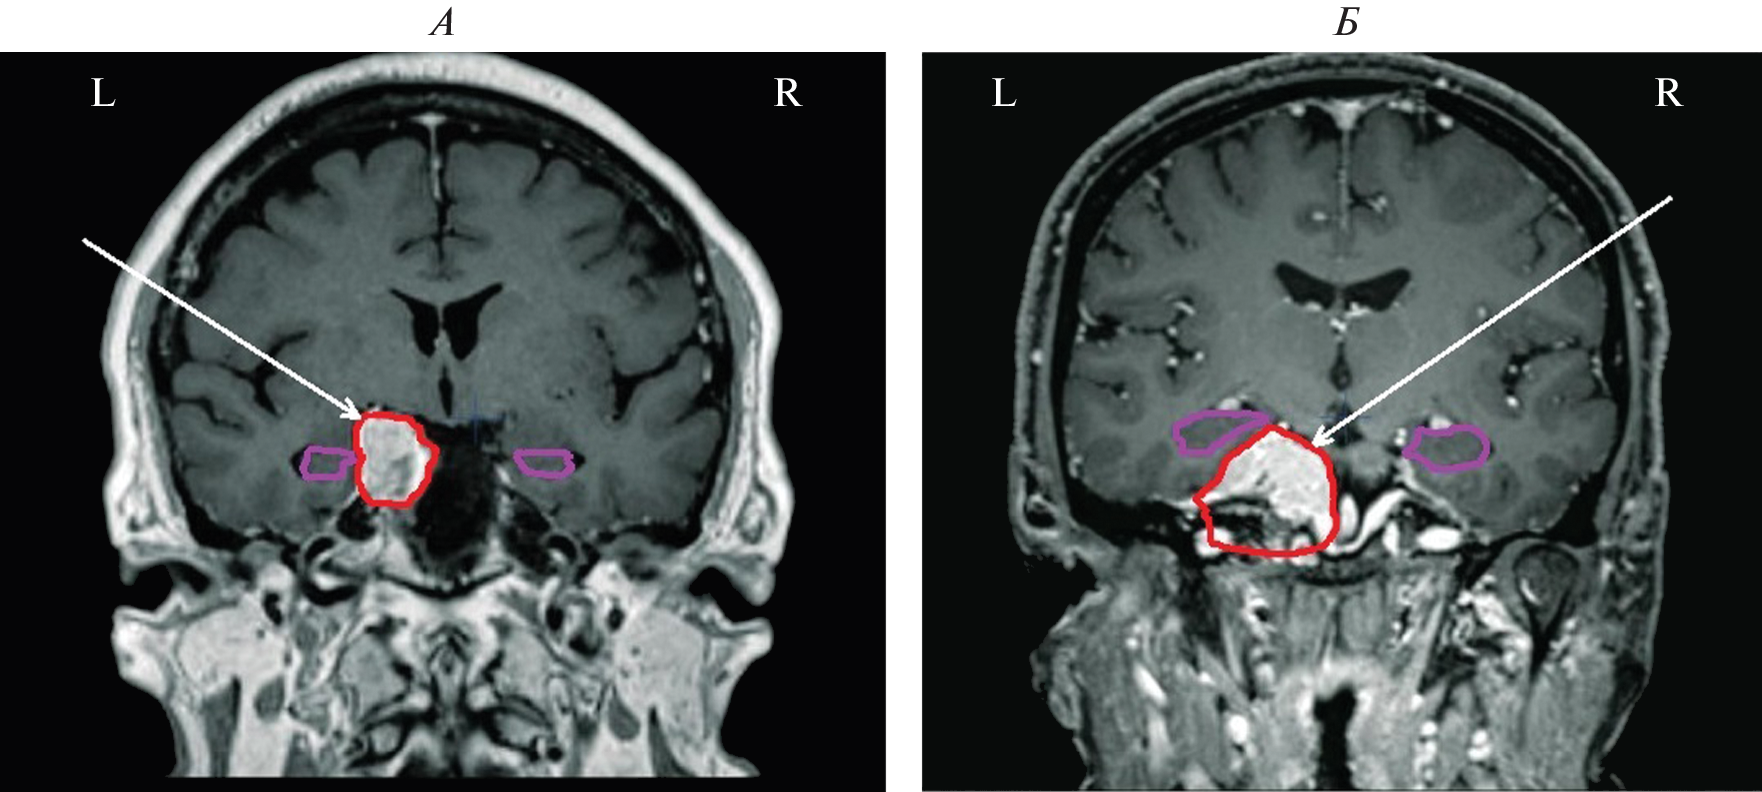

We studied the features of EEG and visual memory processes in 27 patients with a mediobasal regions extracerebral tumor of right and left hemispheres. According to neuroimaging (MRI) and morphometry, the degree of hippocampus involvement in pathological process was assessed. The predominant concentration of irritative-epileptiform signs in the affected hemisphere, as well as the presence of atypical alpha-rhythm episodes in the tumor projection zone, were classified as EEG markers of tumor compressive effect on the hippocampus. Signs of non-identical involvement of the right and left hippocampi in the pathological process were found in the form of a predominance of irritative signs in the left hemisphere throughout the group as a whole. Equivalent dipole sources (EDS) of atypical alpha rhythm are more confined to hippocampal structures than irritative EEG patterns. Neuropsychological testing of visual memory did not reveal significant disturbances in memory processes at this stage of the disease.

- Болдырева Г.Н. Атипичные формы церебральной альфа-активности при поражении регуляторных структур мозга человека // Физиология человека. 2018. Т. 44. № 3. С. 14. Boldyreva G.N. Atypical forms of cerebral alpha activity when human brain regulatory structures are damaged // Human Physiology. 2018. V. 44. № 3. P. 246.

- Болдырева Г.Н., Шарова Е.В., Коптелов Ю.М. и др. Исследование генеза патологических паттернов ЭЭГ при опухолевом и травматическом поражении мозга человека // Физиология человека. 2005. Т. 31. № 1. С. 24. Boldyreva G.N., Sharova E.V., Koptelov Yu.M. et al. Study of the genesis of pathological EEG patterns in tumor and traumatic lesions of the human brain // Human Physiology. 2005. V. 31. № 1. P. 18.